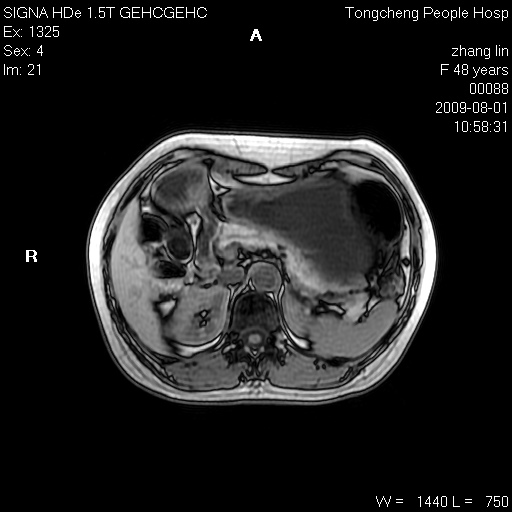

女,48岁。健康体检,彩超发现右肾占位性病变。平素健康。

临床诊断:右肾占位性病变,性质待定(囊肿?肿瘤?)。

上中腹部mr平扫+增强扫描,图像如下:

右肾上极见一类圆形病灶,t1wi呈等信号t2wi呈等高混杂信号,三期增强无强化,边界清---考虑囊肿出血。

同反相位均表现为等信号,病变无强化,考虑含蛋白的囊肿可能,弥散加权相或许有些帮助,